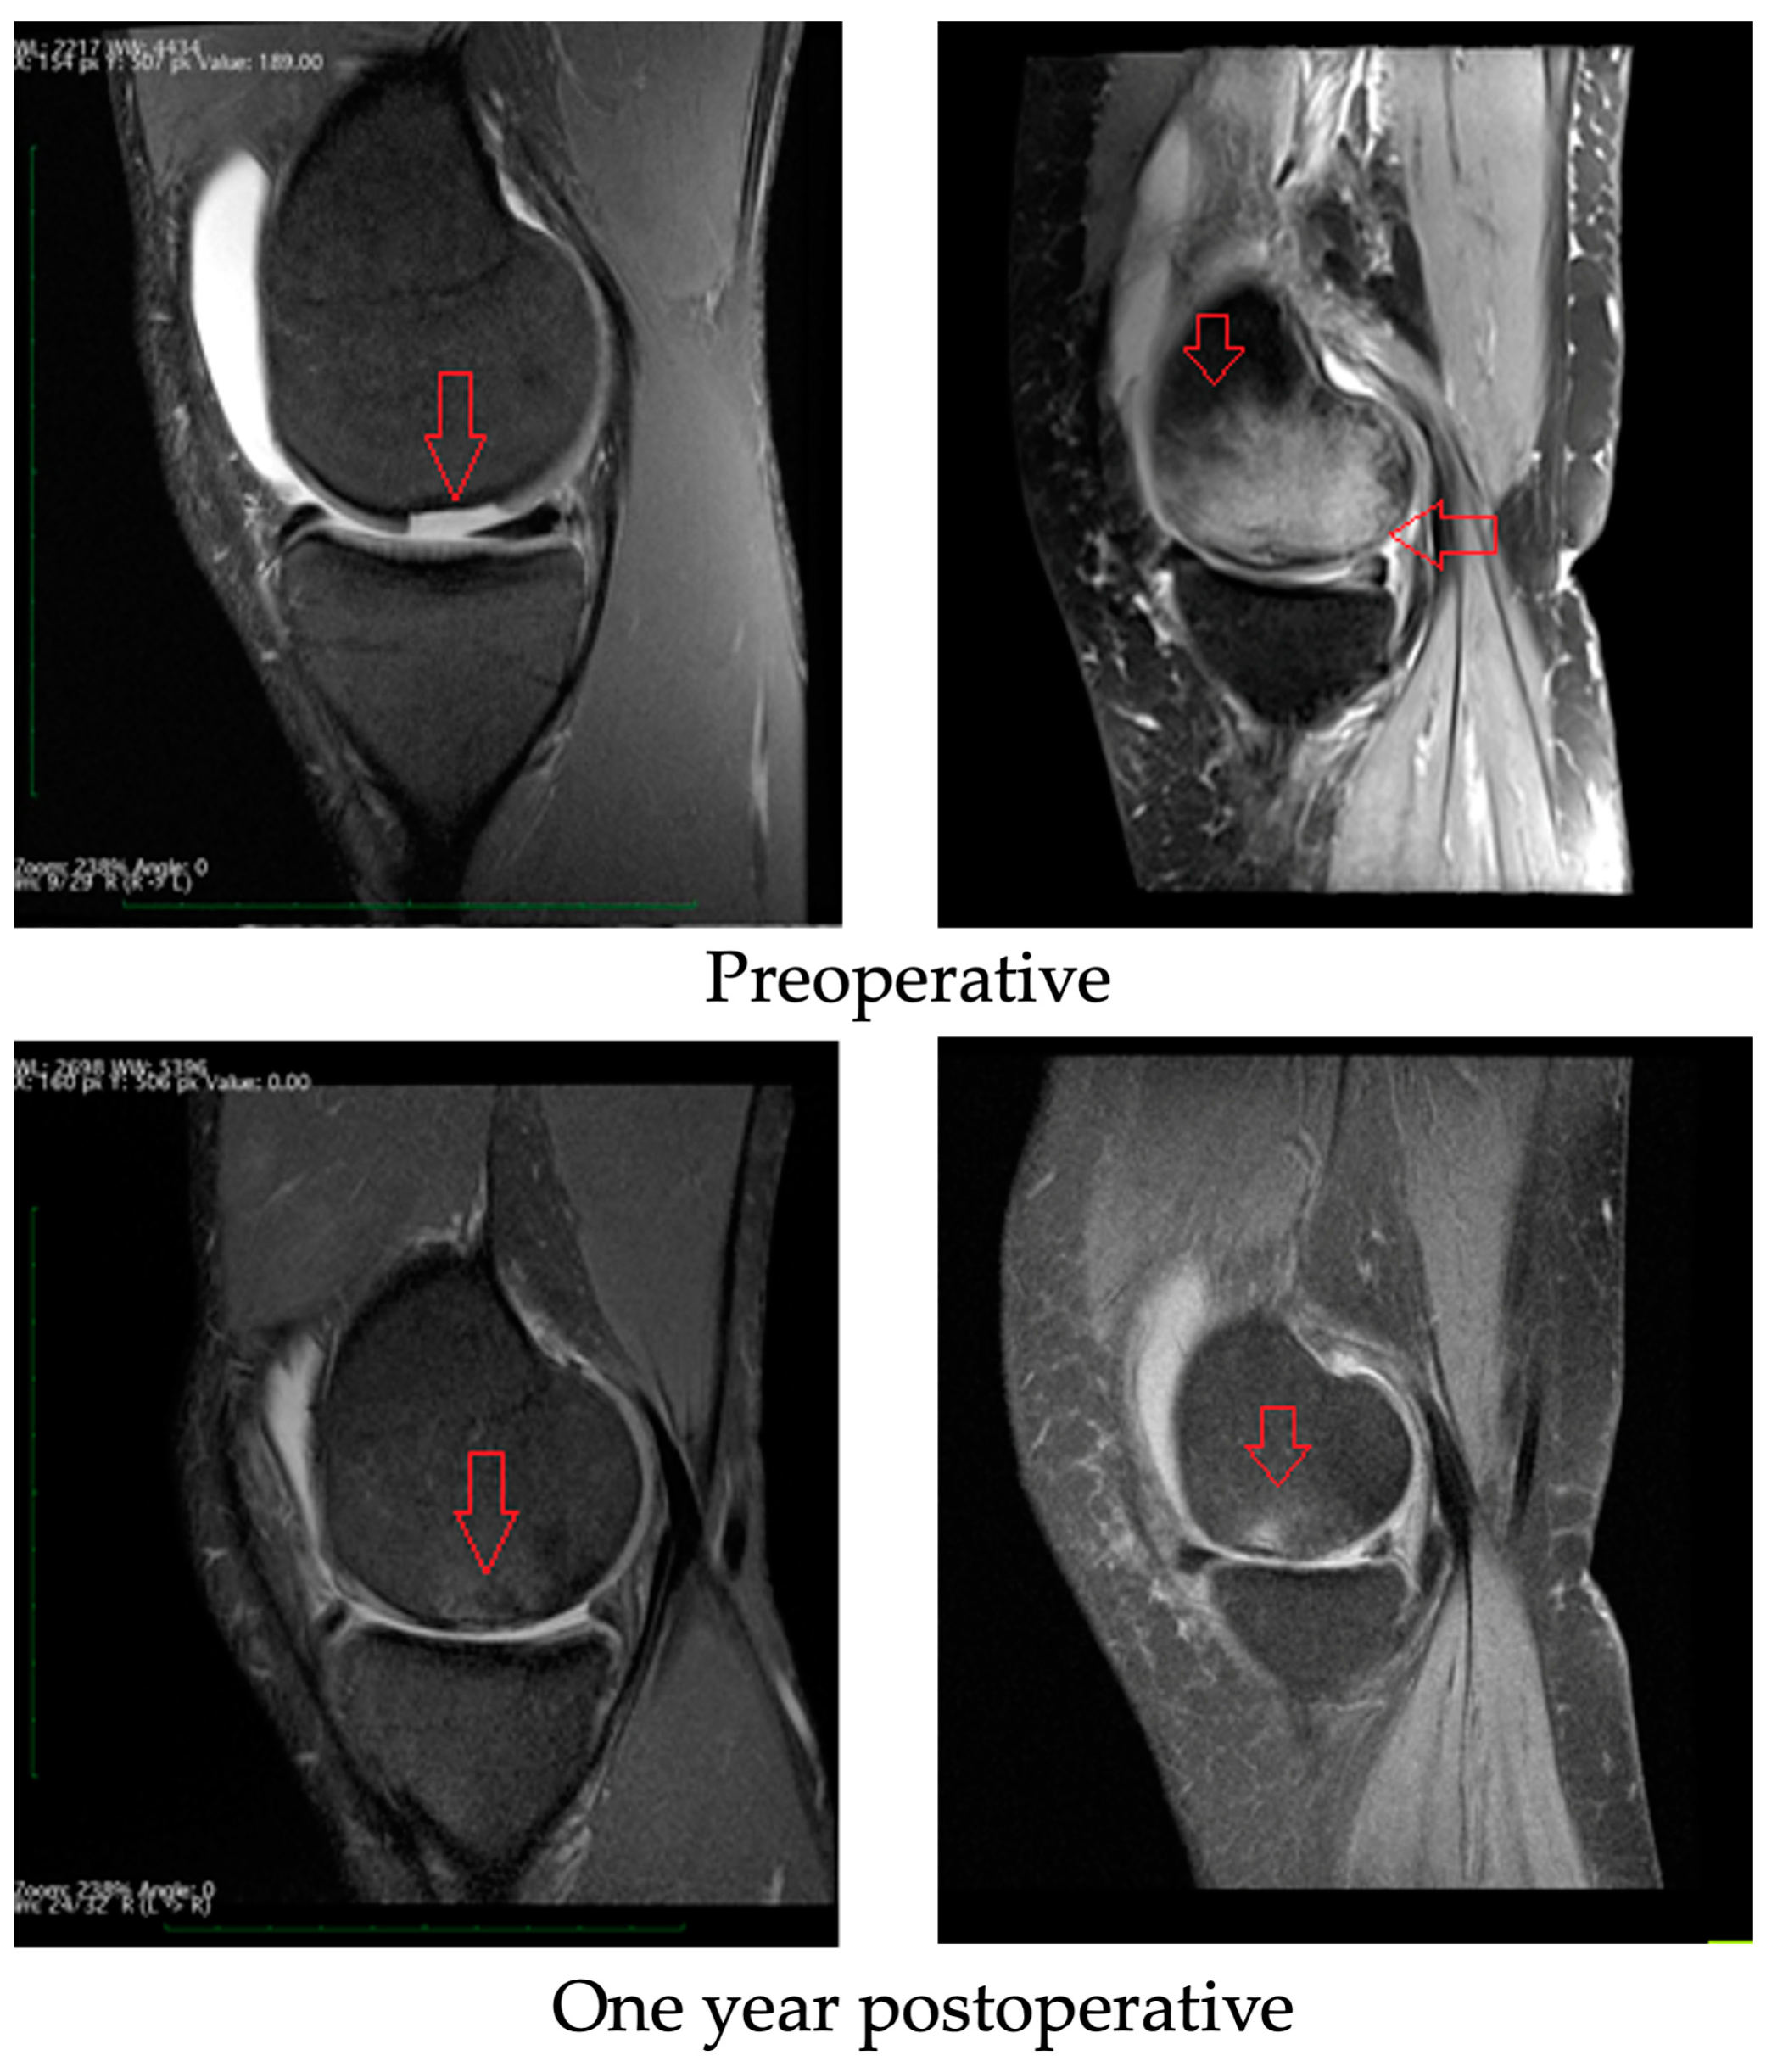

3.3. Radiological Evaluation